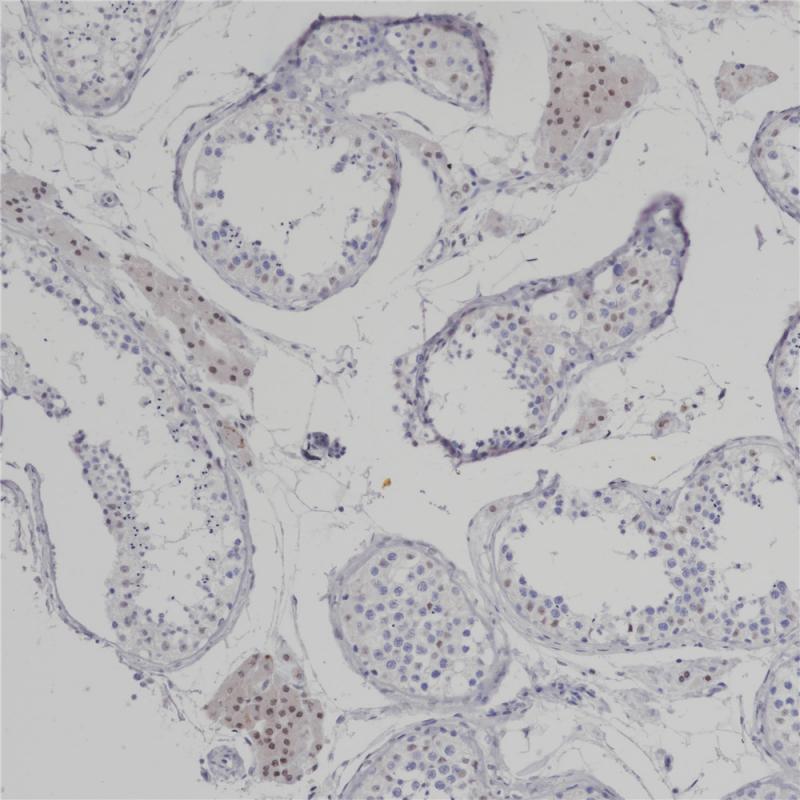

转录因子OVO-like zinc finger 2(OVOL2)包含一个C2H2锌指四分体的锌指结构域,具有可变的N端和C端延伸,起到转录调控的作用。OVOL2在维持上皮谱系的特性中起关键作用。它还通过直接抑制MYC和NOTCH1来抑制细胞周期和角化细胞的终末分化。OVOL2在人类正常组织的睾丸、卵巢、心脏和骨骼肌中表达。研究表明OVOL2是一种结直肠肿瘤抑制因子,通过阻断WNT信号传导来减少结直肠肿瘤的进展和转移。此外,OVOL2被证明可以直接抑制几种糖酵解基因的表达,阻断Warburg效应和乳腺肿瘤的生长和转移。

阳性对照

结肠癌

亚细胞定位

细胞核